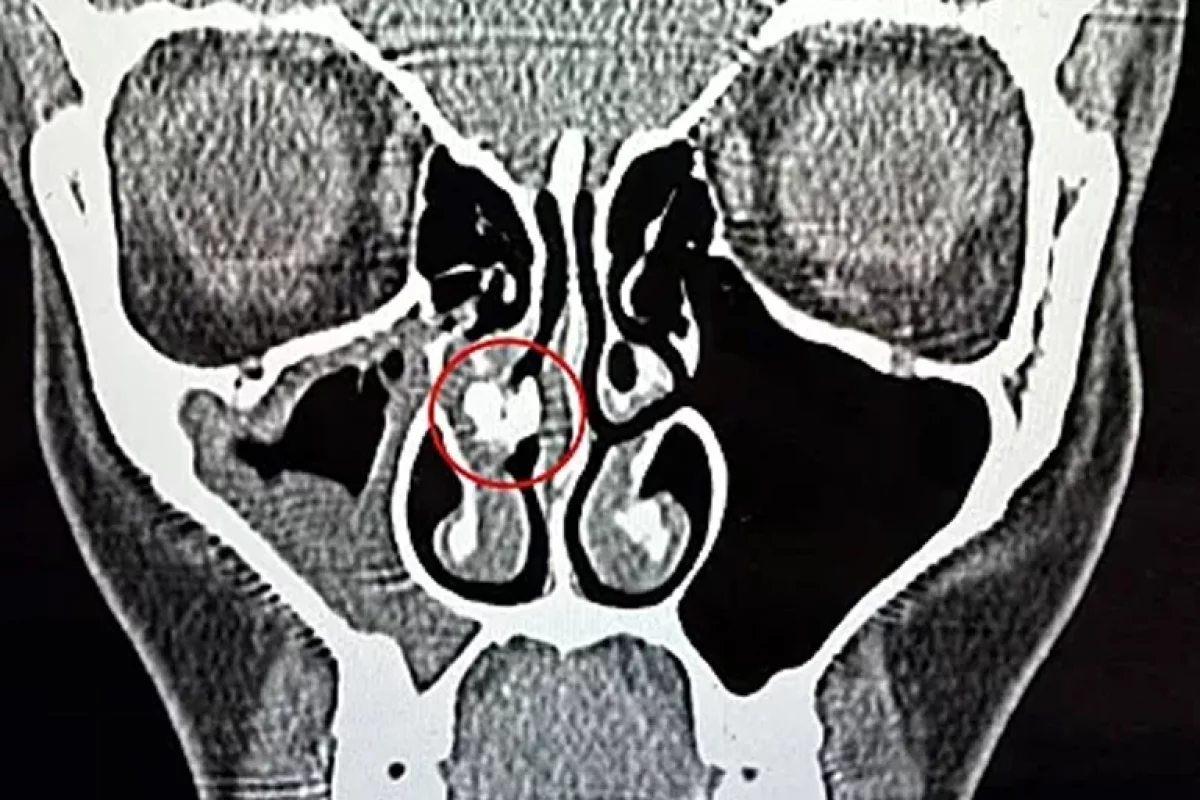

Переломным моментом стал 2025 год, когда женщина обратилась в больницу с синуситом. После компьютерной томографии врачи выявили в её носовой полости инородное тело. Спустя час его извлекли пинцетом — им оказался кусок клейкой ленты. Рейбо показала находку в TikTok и призналась, что не понимает, как скотч оказался в её носу и сколько времени он там находился.